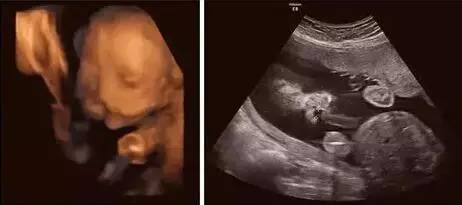

超声影像(四维彩超),帮你排除宝宝先天缺陷